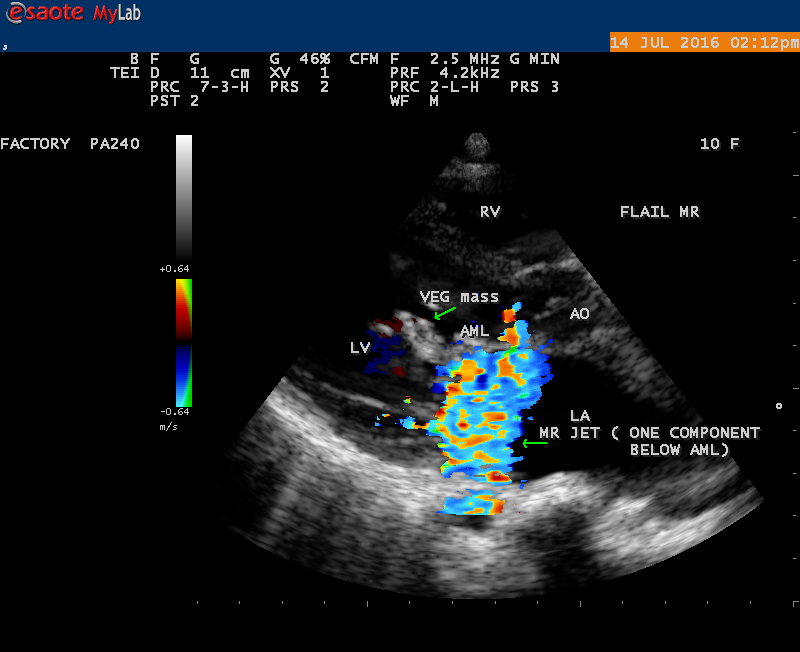

A 10 year female child was referred for echocardiographic evaluation with an apical systolic murmur. The child was having recurrent episodes of rheumatic fever (febrile illness with joint pains) at the age of 5-6 years and taken some treatment from the local medical practitioner, but she was not taken penicillin prophylaxis earlier. The child was remained afebrile for long period and no precipitating factors of infective endocarditis such as dental or genitourinary procedures in the past. General examination revealed normal growth and development, no cyanosis and clubbing and peripheral signs of infective endocarditis such s Osler’s nodes, Janeway lesions, Roths spots and splinter haemorrhages are not present and they are relatively rare in children. Physical examination revealed a grade 3/6 , blowing, high pitched, holosystolic murmur with a constant intensity and duration on dynamic auscultation and loudest at the apex with a radiation to left axilla and transmitted to the left infrascapular area and vertebral coloumn and it is due to the flow generating the murmur is directed posterolaterally within the left atrial cavity, suggesting the murmur of mitral regurgitation due to the rupture of chordae tendineae of anterior mitral leaflet. Blood culture revealed normal. Blood chemistry revealed the positive serum ASO titer, suggesting a recent streptococcal infection and other parameters are normal. X- ray chest reveled moderate cardiomegaly and ECG revealed a left ventricular volume overload pattern of eccentric hypertrophy due to LV dilatation as a result of severe mitral regurgitation and a normal rhythm. Transthoracic echocardiography revealed a giant vegetation ‘popcorn’ like in Figures 1,3 and 4 and ‘cucumber’ like in Figure 2, mainly attached to base and apical portion of anterior mitral leaflet as shown in Figure 31 and manifested in various size and shapes as shown in Figures 1 to 33. A flail anterior leaflet with a disorganized mitral regurgitation jet as shown in Figure 16 and 21 and the posterior leaflet is embedded with vegetation and resulting in ‘kissing forms’ as shown in Figures 13, 14 and 15 in echocardiography imaging. Tricuspid valve is also thickened and calcified as shown in Figure 2 in addition to thickened and calcified mitral leaflets, suggesting an underlying rheumatic etiology predisposing to the formation of vegetation. The child was given 1.2 million units of intramuscular benzathine penicillin injection as a therapeutic and initial prophylaxis dose for rheumatic fever and advised every 3 weeks for life long. Small doses of digoxin and diuretics are also prescribed and advised early surgery (mitral valve replacement) Transthoracic 2D images are as in Figures 1 to 33 are given below

The most common and direct evidence of infective endocarditis is the vegetation and it begins as a microscopic focus of infection and gradually grows into a conspicuous mass. It is typically an irregularly shaped, highly mobile, echogenic mass attached to the free edge of a valve leaflet ( most commonly at the coaptation line) and tends to develop on the ‘upstream’ side of the valve leaflets ( ie, the ventricular side of aortic valve and the atrial side of mitral and tricuspid valves. They may be seesile or pedunculated, but usually has an oscillating or fluttering motion, a typical feature of most vegetations. Vegetation move with the leaflet in a more chaotic (‘oscillating’) manner and it may prolapse through the valve into the LV (left ventricle) as it opens as shown in Figures 3, 4 and 16 and into LA (left atrium) as it closing (Figure 5 and 6) . The mass of vegetation is typically homogeneous with echogenicity similar to that of the myocardium. The infectious process often alter the valvular structure and function. Extensive involvement of the leaflet may result in chordal rupture, leading to severe regurgitation as shown in Figure 21 . Direct and typical signs of RMCT (ruptured mitral chordate tendineae) were chain-flail or whiplash-like changes and had an incidence of 86.7%, causing severe regurgitation and mitral chordal rupture is the leading cause of flail mitral leaflet[30]. A large vegetation may obstruct the valve orifice as shown in Figure 1 and 2 , sometimes termed as “obstructive-type bacterial endocarditis” and producing a functional valve stenosis ( Ping-Pong mitral stenosis [31]) similar to left atrial myxoma as shown in Figure 29.

The shape and size of vegetation are quite variable and mostly it is polypoid [32]. The typical vegetation is a ‘sessile’ or ‘ pedunculating’ valve – attached mass. A ‘sessile’ vegetation had to be completely attached to the valve as shown in Figures 34 and 35 in a 63- year old male, in which a large vegetation is attached to the atrial side of anterior mitral leaflet [33-Figure 13.3-A], producing severe mitral regurgitation as shown in Figure 36 and a mobile vegetation showed a pedunculating part prolapsing into the ventricle as shown in Figure 3 and 4 or atrium as shown in Figure 5 [33-Figure 13.1] in a 10-year old female child. A vegetation was considered as ‘definite’ when shaggy echoes in the M-mode study as shown in Figure 20 . and a corresponding mass without restricted valve motion in the two-dimensional echocardiogram were found as shown in Figure 16 and 30 [33-Figure 13.7]. The vegetation vary in size, often being just a few mm and sometimes reaching to 2-3 cm. A vegetation must be atleast 3 to 6 mm in size to be reliably seen. The mean size of vegetation was 0.6 mm (range 3 to 28) and vegetation > 10 mm in diameter was defined as ‘large’ and those ≤ 10 mm in diameter was defined as ‘small’ and ≥ 15 mm is ‘very large’. Vegetations resulting from fungal infections (candida, aspergillus) are usually much bigger than bacterial vegetations and can be so big to be mistaken for a cardiac tumor. The large vegetations are at increased risk for embolic complications [34], especially on the anterior leaflet of the mitral valve with mobility [35]. A vegetation size of 3.2 x 4.4 cm is called as ‘giant vegetation’ on the mitral valve with a fibrillary appearance of the mass [36- Figure 3] as shown in Figure 1 is an important predictor of embolic phenomena in patients with infective endocarditis causing severe mitral regurgitation as ‘Duck’ shaped jets (Figures 24 and 25 ), disorganized (Figure 21) and sometimes the regurigitant jet splits into two components as one into LA and the second one into LV simultaneously as a bileaflet jets (Figure 10 ) similar to bileaflet structure of AML with vegetation masses (Figure 9 ) . The size of the largest vegetation reported on the mitral valve in the literature in patients with bacterial endocarditis is 7x4 cm[37]. In a study of Nunes, et al[38], vegetation size >13 mm was the only independent predictor of mortality, but some studies [39],[40] did not had an increased embolic risk in patients with vegetation focused only on its presence and size and not on their location. Embolic complications may occur in infective endocarditis(20.6%)and were not more prevalent in the groups with large vegetations [41]. However, Wong, et al [42] found an increased need for surgery in patients with a large vegetation (>10 mm).

The size and shape of vegetation vary due to curling of vegetation. The size of vegetation in this child is 35.6 x 9.3 mm as in Figure 17 , 20 x 23.7 mm as in Figure 1 , 32.9 x 13.9 mm as in Figure 2 .

The shape of vegetation varies in this child as ‘popcorn’ like (Figures 1,3 and 4 ), rod-shaped (Figure ), basket shaped (Figure 7 )[33-Figure 13.3], ‘baby in hand’ appearance (Figure 18), ‘cucumber shaped (Figure 2 ) and a ‘bunch of plantain’appearance (Figure 33 ), ring shaped (Figure 19 }, bileaflet structure (Figure 9 )with bileaflet MR jet as shown in Figure 10 . and kissing forms (Figure 13 - parasternal long axis view, Figure 14 - apical four chamber view and Figure 15 - short axis view)

The anatomic disruption of a portion of the mitral valve apparatus dueto the underlying rheumatic valvulitis with predisposing infective endocarditis which form a vegetation , resulting an eccentric regurgitation jet with orientation opposite in direction of the leaflet having the anatomic defect such as ‘flail’. In the presence of ‘flail leaflet’, the mitral regurgitant spectral signal may have an atypical appearance and the flail portion oscillate in the spectral signal of regurgitant flow stream to produce a ‘tiger stripe’ appearance as shown in Figure 27. associated with ‘whistling’ sound on auscultation[33-Figure 11.85]. The mitral regurgitation (flail MR) jet is chaotic as shown in Figure 26, highly eccentric (Figure 22) and disorganized with one component behind the anterior mitral leaflet and the second component directed towards posterior immediately as in Figure 21 [33- Figure 11.79].